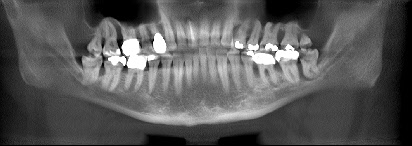

Panoramaaufnahme Parodontologie

Zahntaschenbildung

Knochenabbau zwischen Zähnen

horizontale und vertikale Knochentaschen